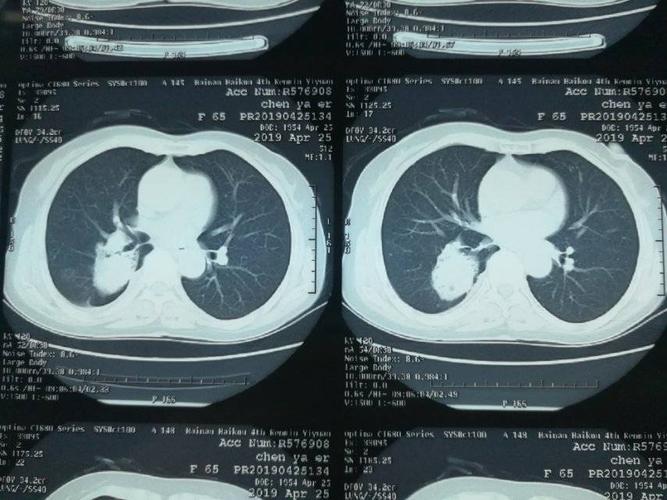

状结节(微浸润性结节)右肺下叶外基底段树枝状结节(微浸润性腺癌)7

右肺下叶背段占位

右肺下叶前基底段

右肺下叶后基底段图片

右肺下叶前基底段图解

右肺下叶背段位置图

右肺下叶内基底段图示